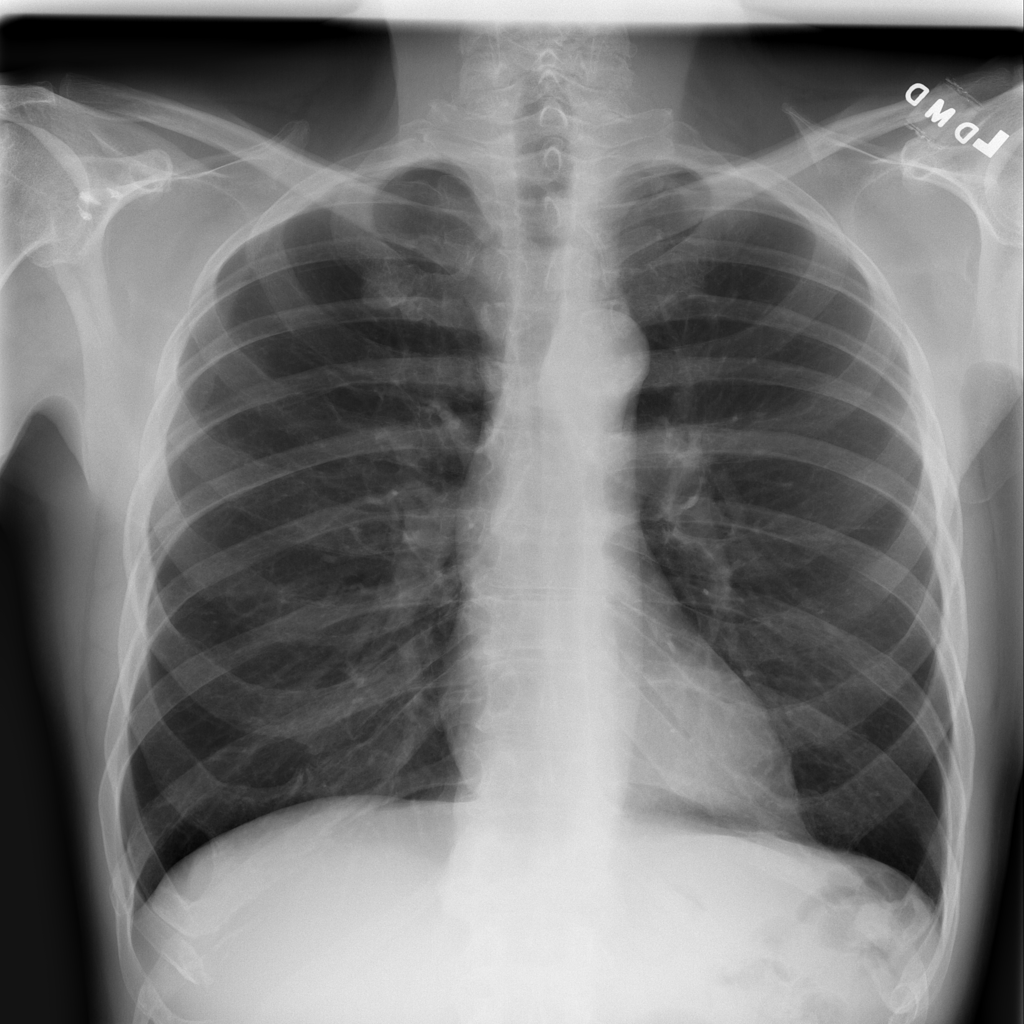

PAT-894B · IMG-000Emphysema

PAT-894B · IMG-000

PA